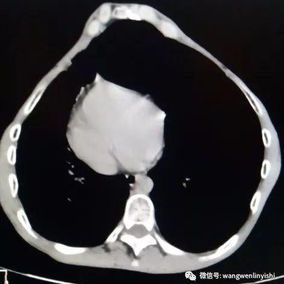

After a preoperative examination, it is observed that the patient's anterior chest wall protruded severely, reaching its peak at the xiphoid process, which presented as a 90-degree angle when viewed from the side. The heart is displaced to the right chest cavity, and the torso is severely deformed, characterized by a broad chest and a noticeably narrowed waist and abdominal area. The narrowing is most pronounced above the pelvis. Moreover, a chest CT scan reveals two large cysts located between the heart and the anterior chest wall in the lower lobe of the left lung, measuring 7x8 cm and 9x10 cm respectively.